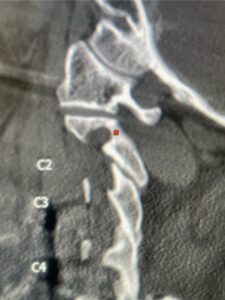

Patient had an existing peripheral occipital nerve stimulator and therefore we had ordered a myelogram since it was not MRI compatible. The patient underwent a decompressive laminectomy and in situ fusion at C2-3. Care was made to preserve a good portion of the C2-3 facets bilaterally. It was felt that her C2 pars anatomically were not favorable to accept pars screws given the proximity of the vertebral foramen with a resultant narrow par (Fig. 2). She also had a normal C2-3 vertebral alignment. Post-operatively she had improvement of her arm pain and strength in right arm. In this case we made a decision to decompress the patient posteriorly given her prior anterior surgery, a more difficult approach to C23 disc space, and significant C23 disc collapse. A posterior approach was favorable in our opinion given the prior posterior surgery was more inferior with less scarring likely to be encountered in the C1-3 region. A posterior decompression also can yield a more adequate spinal cord decompression. Since we elected not to place pars screws because of her anatomy, and perform an in-situ fusion, careful attention was made to preserve as much of the C23 facet complex as possible.

Fig 1: Sagittal cervical CT myelogram demonstrating spinal cord compression at C2-3 above the prior anterior cervical fusion (red arrow)

Fig 2: Sagittal cervical CT pyelogram demonstrating a very narrow C 2 pars and prominent vertebral foramen making in unsafe to place a pars screw